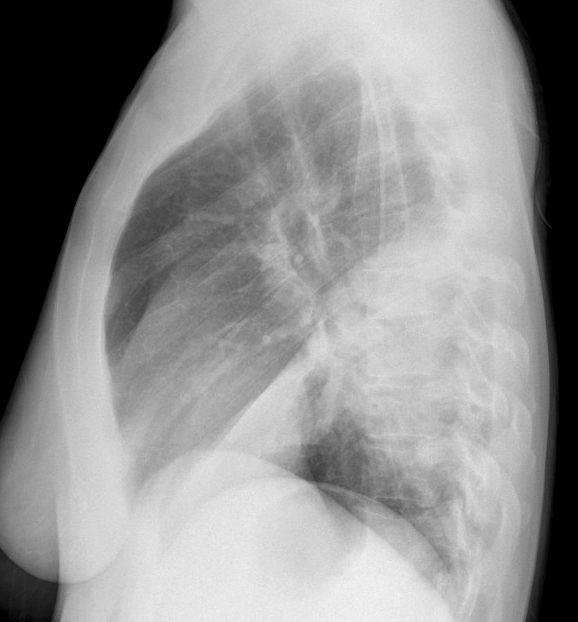

Gallery Pneumonia Case 11 RLL pneum Lat

Case 11 RLL pneum Lat